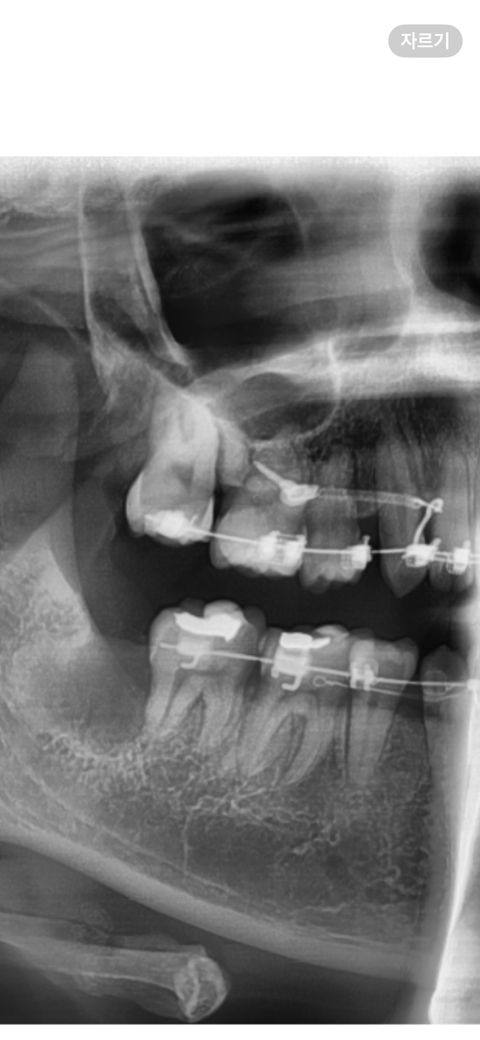

상악 어금니 사이 크게 어두운 삼각형부분 잇몸뼈가 흡수된건가요? 교정중 각도때문에 저렇게 보일수있는건지 적극적인 치료가 필요한 상황인지 걱정되고 궁금합니다. 교정하면서 언젠가부터 저부분 블랙트라이앵글이 생겼습니다.

최근 사랑니를 뺐는데 사랑니치과원장님, 교정치과원장님, 동네치과원장님 모두 이 엑스레이를 보셔도 이부분에 대해서 별 말씀은 없으셨습니다. 예전에는 이렇지 않았던것같은데 어떤 상황과 연유로 저렇게 보이는건가요?

파노라마 사진 각도 떄문에 그렇게 보일수 잇고 저 부분은 치아 사이가 보이는거일수도 있습니다.

교정을 할 때 일시적으로 치아에 과도한 교정력이 가해지게 되면 치아가 치조골에서 분리가 되면서 사진처럼 빈 공간을 보일 수 있습니다. 대부분 교정이 진행되면서 해당 부위는 치조골로 차오르기 때문에 너무 걱정하지 않으셔도 될 것으로 생각됩니다.

자세한 확인을 위해서 치과에서 진료를 받아보는 것을 권유드립니다.

엑스레이 사진 비포, 애프터가 있다면 좀 더 비교하여 도움되는 답변을 드릴 수 있을 것 같네요. 보통 교정 중에는 잇몸, 잇몸뼈가 흡수되는 경향이 있습니다.